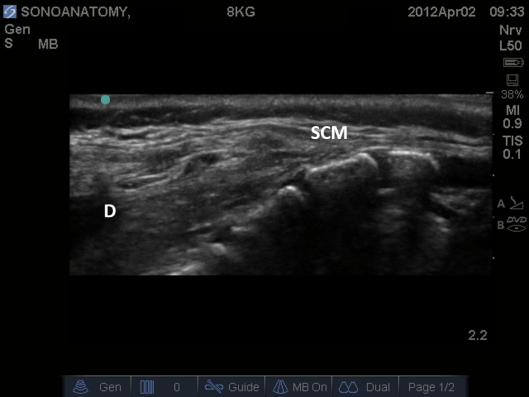

Fig 5. Ultrasound Probe in Midline Longitudinal Plane over sacrum. D – dura, SCM – sacrococcygeal membrane